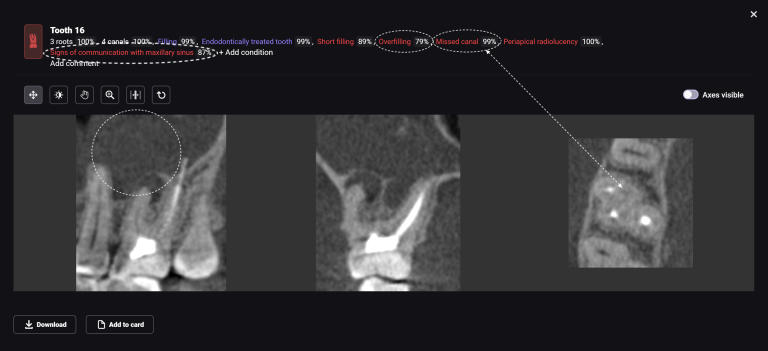

Task: Plan the implant treatment for the replacement of teeth 16 (Universal 3) and 17 (Universal 2), reduce the time required for surgical template fabrication, and improve the accuracy of its fit. Using the “STL” module of Diagnocat, it is possible to create a 3D reconstruction of cone-beam computed tomography (CBCT) and virtual models of templates. To achieve this, intraoral scan data is uploaded into the module, and a suitable CBCT is selected for merging.

Problem:In some clinical cases, it’s difficult to ensure the required accuracy in merging intraoral scanning and CBCT.

Solution: Diagnocat AI provides an advanced solution for identifying CBCT structures using machine learning and artificial intelligence technologies. By combining STL and DICOM data in a unified coordinate system, Diagnocat minimizes errors when creating template models.